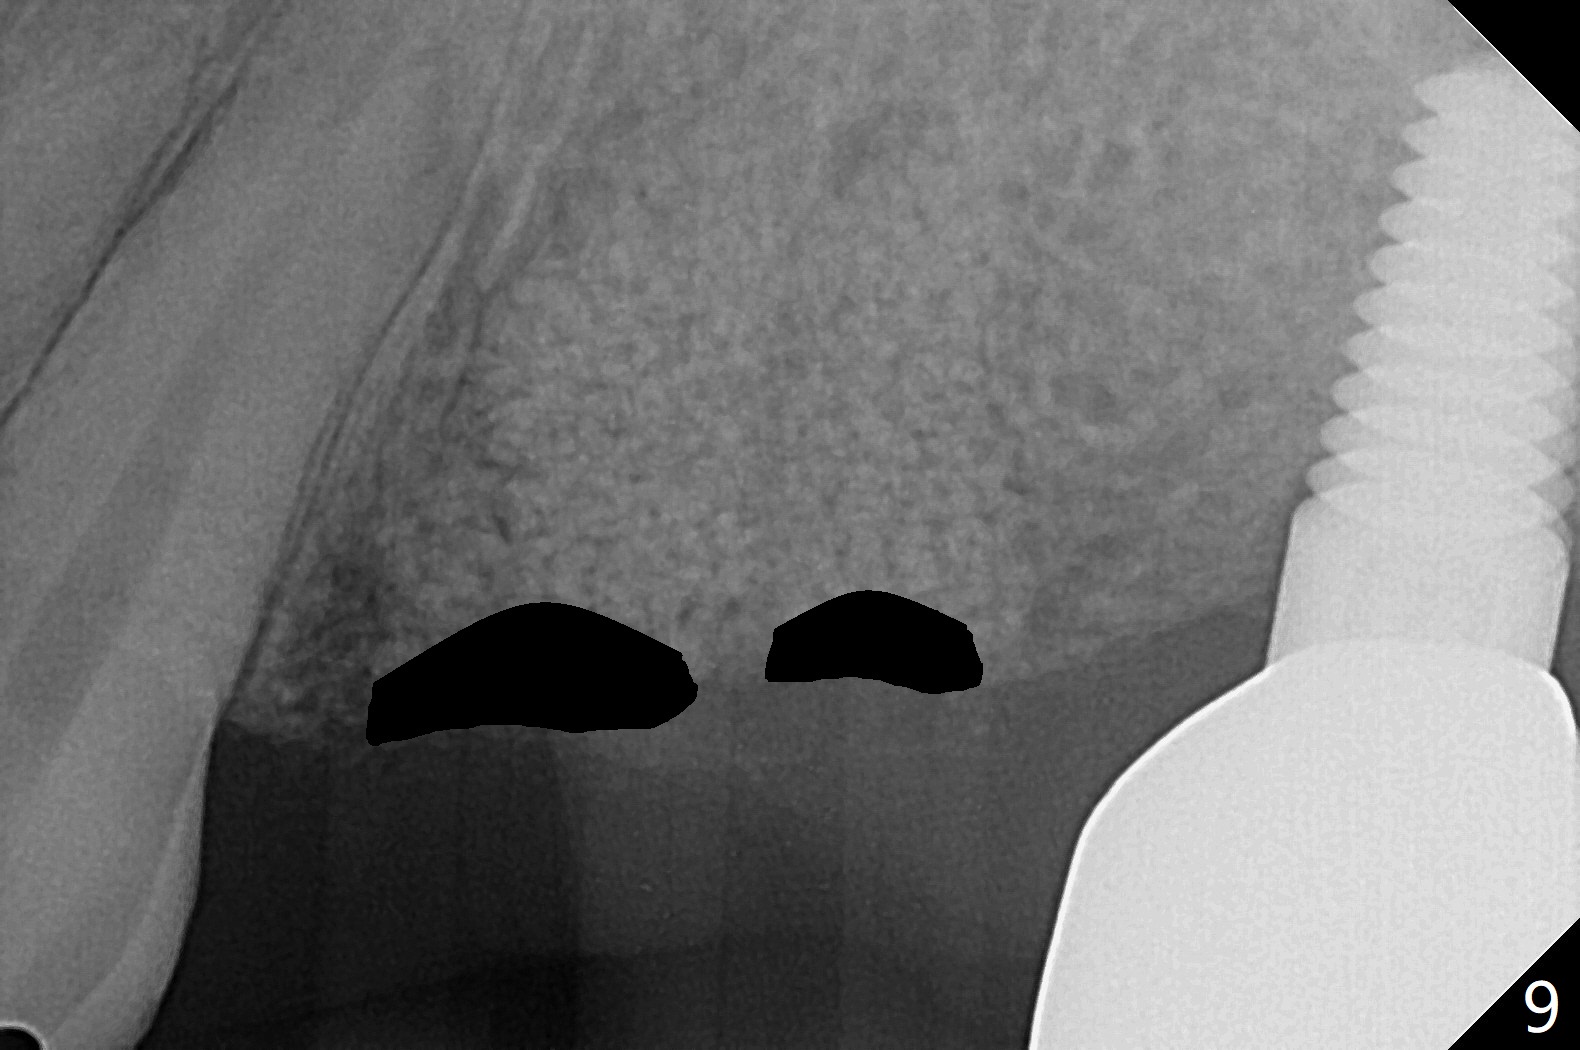

42岁女,12号牙断裂(图一),在拔除中不幸损伤13号牙,一起拔除,用GEM21S与异体骨和人工骨进行位点保存,术后骨粉一直脱落,病人觉得伤口有臭味。术后16天根尖片显示骨粉仍在牙槽窝(图二),伤口尚未愈合(图三),骨粉密度不高(图四,五)。讨论后,决定去除余留骨粉,重新刮拔牙槽窝,反复冲洗,最好放置粘性骨粉(图六),覆盖PRF和不可吸收膜,使用PTFE缝线,树脂敷料。术后三周膜和骨粉仍在原位(图七,八)。为了恢复龈乳头,术后四,五个月,利用导板去除两个牙位牙槽嵴骨质(图九),把植体植入牙槽嵴深部,之间便形成突起的牙槽嵴(图十:C)以及龈乳头。植牙整合后,利用临时牙冠,反复调整,挤压形成比较正常龈乳头。